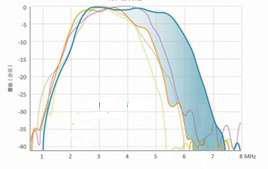

Unique RF Platform

Because of hardware limitations, traditional front-end RF platforms are unable to transmit certain useful information. VINNO’s unique platform is the first in the fast processing power to ensure detailed images and accurate measurements. The RF platform reads a wider range of signals, resulting in clearer, higher-resolution images. This endows the system with unique capabilities, including full screen mode and high-resolution images free of distortion, which aids in diagnosis of small lesions

Xcen Probe Technology

The Xcen high-frequency wideband probe transmits at up 16 MHz and provides clearer images of subtle variations in tissue, which allows lesions to be diagnosed earlier.